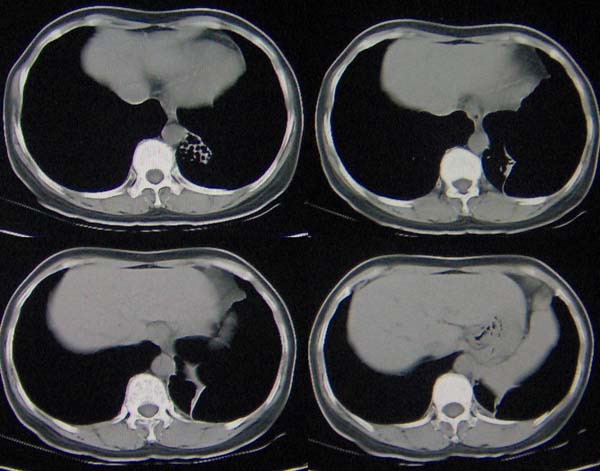

标题: CT9509:女,50岁,咳嗽,发热,38度, [打印本页]

标题: CT9509:女,50岁,咳嗽,发热,38度,

左肺下叶支气管呈囊状扩张。考虑支扩。

左下肺支气管扩张;支气管炎;左下肺纤维条索并局部胸膜肥厚。

左肺下叶支气管呈囊状扩张。考虑支扩。胸膜肥厚\\粘连,建议增强除外肺隔离症.

左肺上叶小片状病灶密度底,左下叶见多发小囊状病灶,周围透光增强无纹理,沿左侧膈肌旁见条带状病灶边界清晰,

1左肺上叶炎症,左下支气管扩张伴感染,肺隔离征待除外,2肺大泡,3左下叶内基底段不张?

左肺舌叶及右肺下叶背段斑片状低密度影,左肺下叶内基底段网格状阴影,周围肺野透亮度增高,结合临床咳嗽、发热,38度,无咯血及反复感染病史,考虑双肺炎症,左下肺发育不良。建议抗炎治疗后复查或增强与左下肺隔离症鉴别。